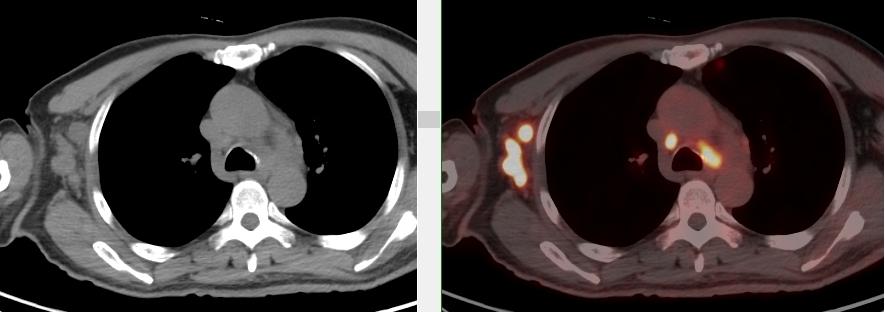

完善PET/CT檢查示:右側腋窩、雙側中下頸部、縱隔、雙側肺門多發MT,建議淋巴結活檢。后患者行右腋窩淋巴結切除活檢術,經北京大學第三醫院病理科會診示:右腋窩淋巴結惡性腫瘤,呈淋巴竇內生長模式,瘤細胞呈上皮樣,異型性明顯,伴中性粒細胞浸潤。結合病史及免疫組化,考慮為SMARCA4(BRG1)缺失的胸部腫瘤,伴神經內分泌標記表達。

本例為罕見病理類型的腫瘤,影像學表現無明顯特異性,診斷困難。強化CT和穿刺病理已基本明確為惡性腫瘤,行PET/CT檢查一是為了全身檢查,完善分期,二是根據PET代謝情況指導進行生物靶區活檢,進一步明確病理診斷。最終,PET/CT除縱隔病變外發現更多頸胸部淋巴結代謝異常,綜合考慮后對腋窩淋巴結進行切除活檢,最終得到病理證實。